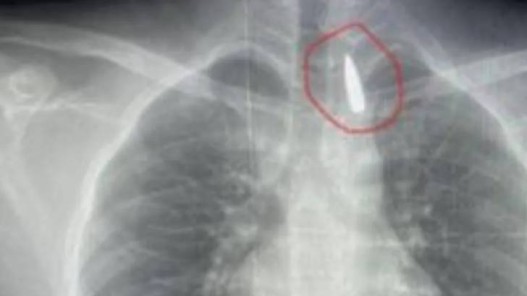

• سلاح في يد مذيعة إسرائيلية يكشف ازدواجية المعايير تجاه الإعلام الفلسطيني

عمان1:أثارت صورة حديثة لمذيعة القناة 14 الإسرائيلية، ماغي تابيبي، وهي تحمل سلاحا من نوع "إم 16" داخل مقر القناة، جدلا واسعا على منصات التواصل الاجتماعي. ونشر الصحفيان ينون مغال وتمير موراغ الصورة التي تُظهر تابيبي داخل غرفة محصنة على ما يبدو، في مشهد وصفه مغردون وصحفيون بأنه كشف صريح للتن...